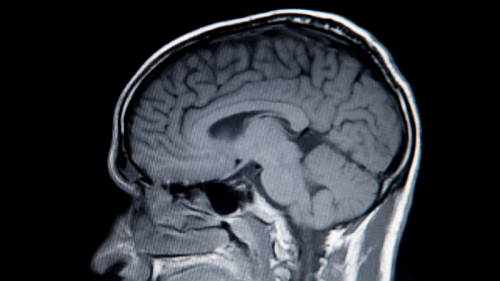

Une lésion cérébrale correspond à une atteinte du cerveau pouvant être provoquée par un choc, un accident vasculaire cérébral, une tumeur, une infection ou un manque d’oxygène. Ses conséquences varient selon la gravité et la zone touchée.

Comme le cerveau contrôle les mouvements, la parole, la mémoire, la vision et les émotions, une lésion peut entraîner de nombreux troubles physiques, cognitifs ou comportementaux. Certains symptômes apparaissent brutalement, d’autres plus progressivement.

Le cerveau commande de nombreuses fonctions essentielles : les mouvements, la parole, la mémoire, la vision, l’équilibre, les émotions et la conscience. Lorsqu’une région cérébrale est endommagée, les symptômes reflètent souvent la fonction de cette région. C’est pour cette raison qu’une lésion cérébrale peut se manifester soit par une faiblesse musculaire, soit par un trouble du langage, soit encore par des changements de comportement. Il n’existe donc pas un symptôme unique, mais un ensemble de signes possibles.